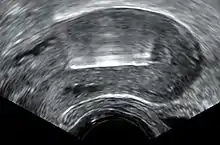

Immediately prior to insertion, the clinician will perform a pelvic exam to determine the position of the uterus.[20] After the pelvic exam, the vagina is held open with a speculum.[36] A tenaculum is used to steady the cervix and uterus.[36] Uterine sounding may be used to measure the length and direction of the cervical canal and uterus in order to decrease the risk of uterine perforation.[37] The IUD is placed using a narrow tube, which is inserted through the cervix into the uterus. Short monofilament plastic/nylon strings hang down from the uterus into the vagina. The clinician will trim the threads so that they only protrude 3 to 4 cm out of the cervix and remain in the upper vagina. The strings allow the patient or clinician to periodically check to ensure the IUD is still in place and to enable easy removal of the device.[20]